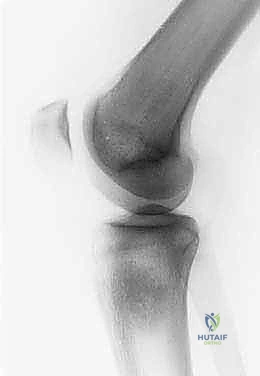

لفهم مدى تعقيد وعبقرية جراحة استئصال الظنبوب القريب، من الضروري الإبحار في أعماق التشريح الأساسي لهذه المنطقة الحيوية. لا يقتصر الأمر على مجرد عظام، بل هو نظام هندسي وبيولوجي متكامل ومعقد. يتكون مفصل الركبة من التقاء عظم الفخذ (Femur) من الأعلى، وعظم الساق أو الظنبوب (Tibia) من الأسفل، وعظم الشظية (Fibula) الجانبي، بالإضافة إلى الرضفة أو صابونة الركبة (Patella) في الأمام. الجزء القريب من الظنبوب هو الجزء العلوي العريض من عظم الساق، والذي يشكل القاعدة الأساسية التي يستند عليها مفصل الركبة ويتحمل وزن الجسم بأكمله.